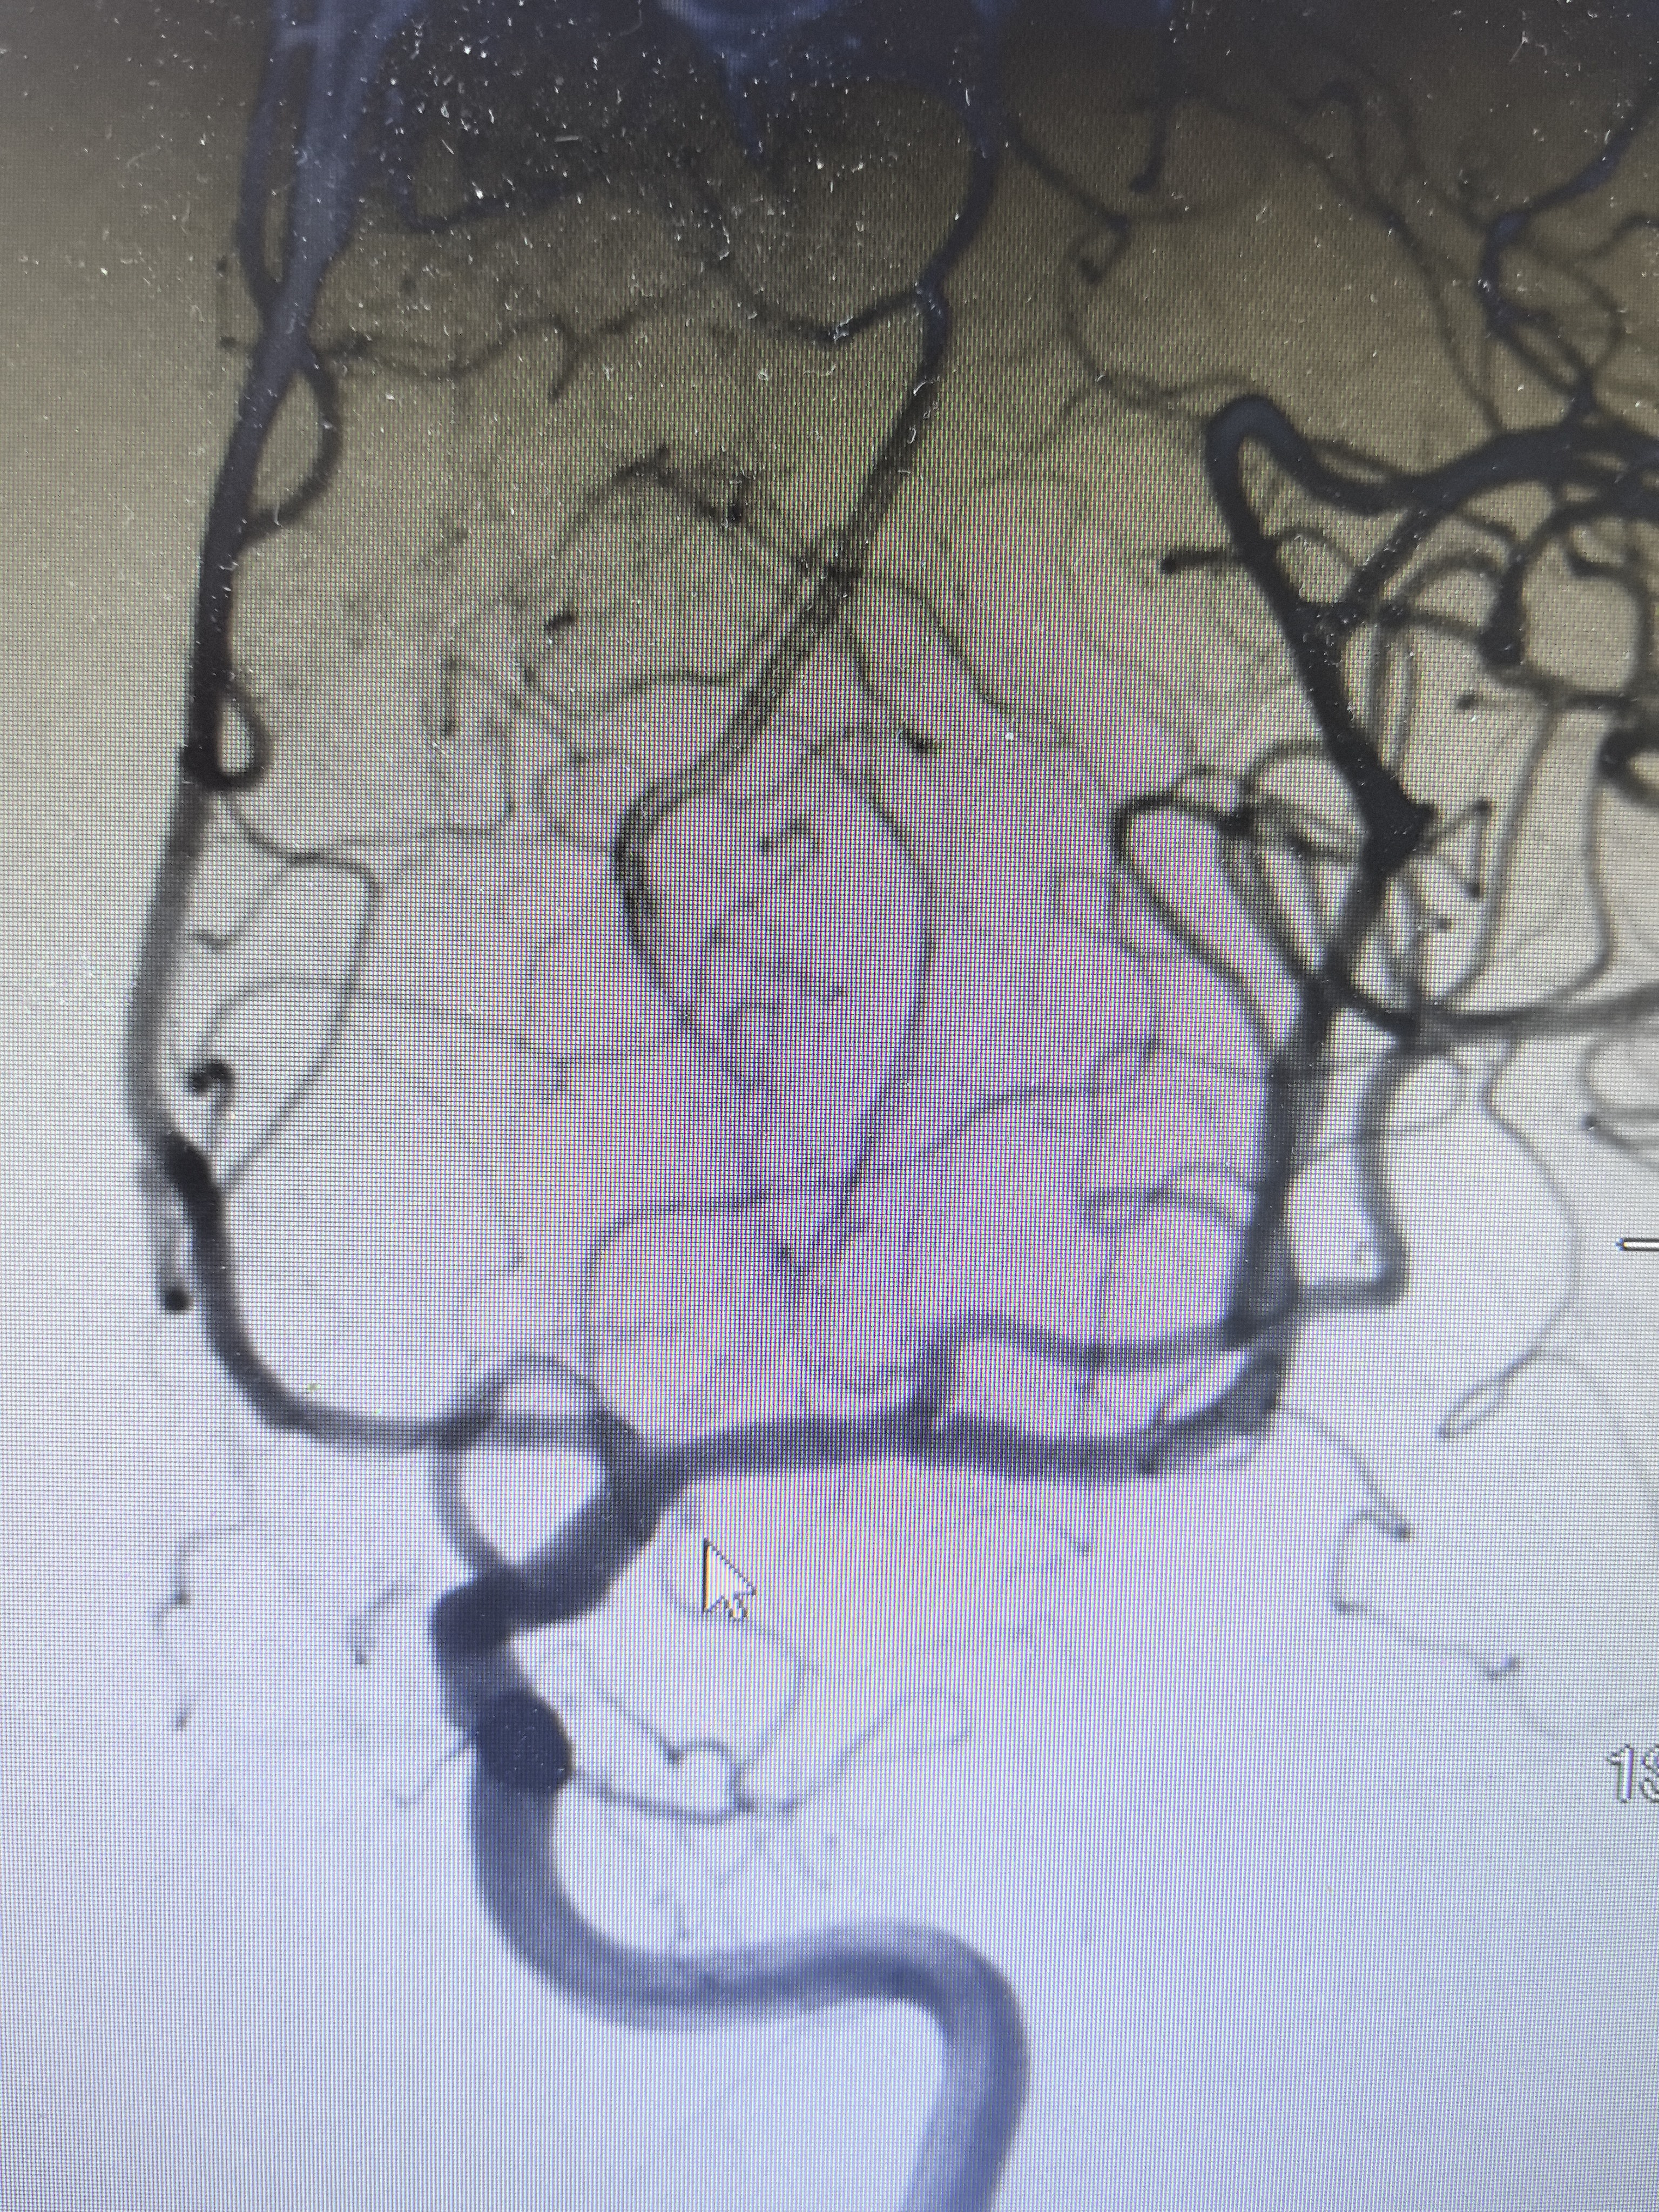

DSA显示左侧变异颞前早期分支起始部微小动脉瘤

路途下显示动脉瘤